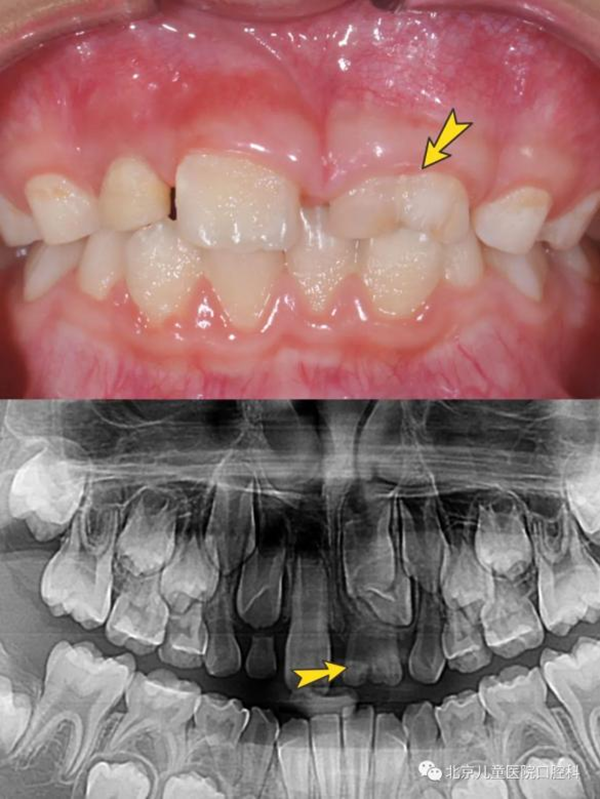

同时,在这个阶段孩子的乳牙逐渐替换为恒牙,有的时候周围的牙都替换了,却只有一颗牙迟迟不松动;有的时候乳牙脱落了很久,新牙还没有长出来;或者新牙长出来却是“扭着身子”的……这有可能是存在多生牙、融合牙、牙齿异位萌出、牙扭转等问题。

乳牙是融合牙(上图),对应恒牙牙胚发育异常(下图)

上颌六龄齿卡在前面乳磨牙颈部,位置低,长不出来(上图),六龄齿位置较为隐蔽,萌出时不替换乳牙,萌出障碍很难发现(下图)